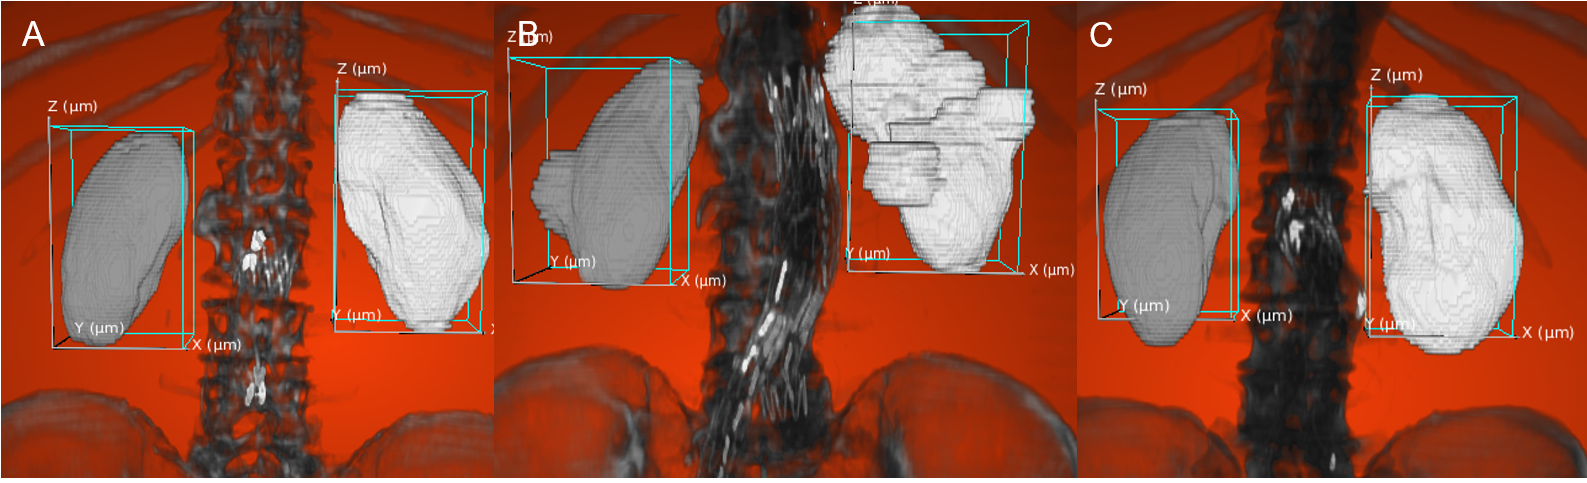

Refer to caption

Figure 2: 3D kidney detection of normal and cystic kidneys. A: Bounding box properly frames the kidneys. B-C: Overflow by the cystic (B) and healthy kidneys (C).

As seen in Figure 2, the 3D boxing is successful, but coarse. The boxes frame the majority of the kidney, but does not fit the organ perfectly. When transferring the results from 2D to 3D, the algorithm usually fails to contain the whole organ as shown in Figure 2B.

Post-processing step unsuited for objects misaligned with axes. One element causing this imprecision is the poor performance of the non-maximum suppression algorithm with non-axis aligned objects. When the kidney is misaligned with the Z axis, the organ overflows the bounding box.

Propagation of error. Another factor leading to reduced performance in 3D detection is the propagation of error from 2D to 3D. If the 2D boxes are not representative of the kidneys, the error will propagate to the 3D boxes. This leads to lower similarity scores for 3D detection.

Inaccuracy with kidney extremities. Detection of the kidney extremities is challenging for the model possibly because of its smaller size or of the decrease in characteristic features. These parts are more likely to fall under the radar as seen in Figure 2C where the lower section of the kidneys was not detected.